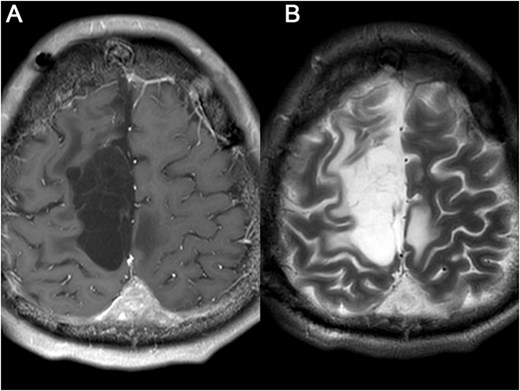

A 23-year-old male presented to our hospital with a 3-day history of episodic left upper limb paralysis. Upon admission, he reported progressive left lower limb motor incoordination, temporal visual field defects in the left eye, bilateral vision,deterioration, and bilateral olfactory hypesthesia over the preceding 3 months. Three days prior to admission, he experienced sudden-onset left upper limb paralysis lasting ~10 minutes before spontaneous resolution. Cranial magnetic resonance imaging (MRI) revealed a giant meningioma (>8 cm in diameter) causing extensive compression of adjacent structures, with marked heterogeneous enhancement on contrast imaging (Fig. 1). Preoperative intracranial vascular embolization was performed, followed by tumor resection via a bifrontal-parietal approach 1 day later (Fig. 2). Intraoperative findings confirmed a tumor >8 cm in diameter with cranial bone erosion (Fig. 3). Postoperatively, the patient developed transient bilateral lower limb paralysis (muscle strength grade 0) on Day 1, which resolved completely within one month. Histopathological analysis demonstrated features consistent with atypical meningioma: sheet-like growth pattern, increased nuclear-to-cytoplasmic ratio, prominent nucleoli, focal necrosis, and immunohistochemical staining showing Vimentin(+), SSTR2(+), PR(+), EMA(−), and a Ki-67 proliferation index of 5%–10%. The patient underwent gamma knife radiosurgery at 6 months and 1 year postoperatively. Three-year follow-up MRI showed no tumor recurrence or significant progression of residual lesions (Fig. 4), with significant improvement in visual acuity, hearing, and visual field deficits.

Brain MRI was re-examined after 5 months (A) and 17 months later (B), respectively, and showed that the residual tumor had not progressed and no other recurrence lesions were found.

Due to the tumor's massive size and hypervascularity, preoperative arterial embolization was performed. While preoperative embolization has been shown to reduce surgical complications and long-term disability rates, conclusive evidence supporting its efficacy in minimizing intraoperative blood loss remains limited [9–11]. Atypical meningiomas exhibit high 5-year recurrence rates of 40%–60%. However, follow-up evaluations at 1 and 3 years in this case revealed no tumor recurrence or significant progression of residual lesions, suggesting personalized treatment strategies may transcend traditional prognostic frameworks. This outcome underscores the efficacy of multimodal therapy (embolization + surgery + radiotherapy) and aligns with the hypothesis that individualized approaches could improve outcomes beyond conventional expectations. Notably, the absence of recurrence at 3-year follow-up contrasts with the typical 40%–60% recurrence rates reported in literature, further supporting the potential of tailored therapeutic regimens.